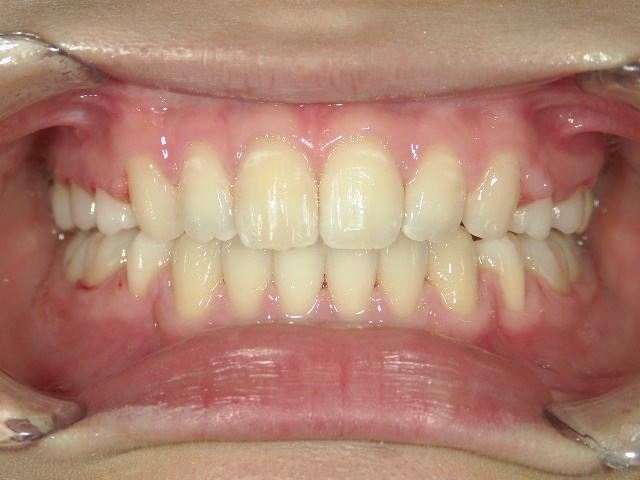

矯正歯科(全顎ワイヤー矯正)治療後

矯正歯科 治療後